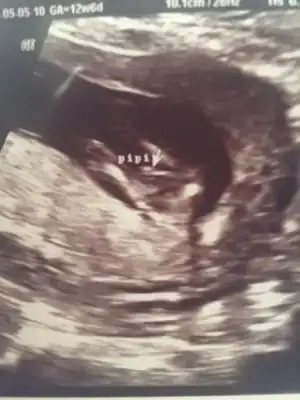

Eki Görüntüle 1854173 merhaba annişler dr geliyorum 11 hafta 2 günlük olmuşuz doktor kız dedi amaa bayramdan sonra netleşir dedi böyle olan oldu mu hiç 11 hafta da kız deyip erkek olan

valla bana 10+2 de kız olabilir dedi.12+6 da kesin erkek dedi Can'ım hatta pipi nin çıktısını bile verdi.

Maşallah bıdığa, burnusu bile belli oluyor annesi. :nazar::nazar::nazar:

Daha tahmin için erken, kız tahminleri ilerleyen haftalarda netleşiyor. Doktor varsayımda bulunmuş sadece.